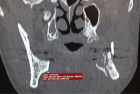

Sagittal split osteotomy (SSO) of the mandible is still an important part of orthognathic surgery, but “bad split” fractures that happen during the surgery are still a big problem. This report describes a rare case of bilateral bad split associated with highly compact mandibular bone (D1–D2 type) in a 53-year-old male undergoing mandibular advancement. The bone was too hard for the piezoelectric and rotary tools to work, and there was very little bleeding. This caused fractures in the cortex and lingual. Postoperative computed tomography confirmed the presence of highly dense bone, correlated with delayed healing and recurrence. Consistent pre-surgical CT scanning for an assessment of the density of the mandibular bone can provide essential information about the potential risk of the osteotomy procedure in the patient. Performing a careful bone quality and density examination pre-operatively will allow the surgeons to select the most appropriate instruments and surgical techniques that will fit the patient’s individual anatomy. Such a point escalates to being very significant when dealing with the geriatric population, as bone density increase can not only alter the fracture behavior but also the recovery process during and after surgery. The inclusion of regular CT-based bone density evaluations into the preoperative routine not only facilitates the anticipation of surgical difficulties but also results in safer and more efficient osteotomies.

Figure 1